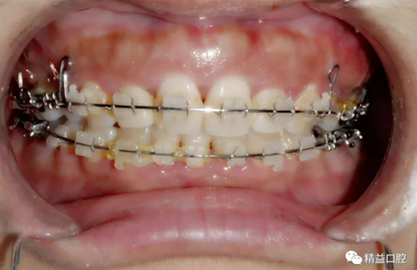

內(nèi)收過程中,李醫(yī)生在上頜左右各植入一顆支抗釘,以達(dá)到更好的內(nèi)收效果。

27歲嚴(yán)重齙牙,上下門牙牙根吸收嚴(yán)重,兩年矯正徹底蛻變,組建幸福家庭

因下頜唇傾比較嚴(yán)重,加上門牙牙根在矯正前已經(jīng)有大量吸收前提下,為了實(shí)現(xiàn)更好的矯正效果,李醫(yī)生選擇了拔除下頜左一,內(nèi)收下牙,給上牙內(nèi)收提供更多的空間。